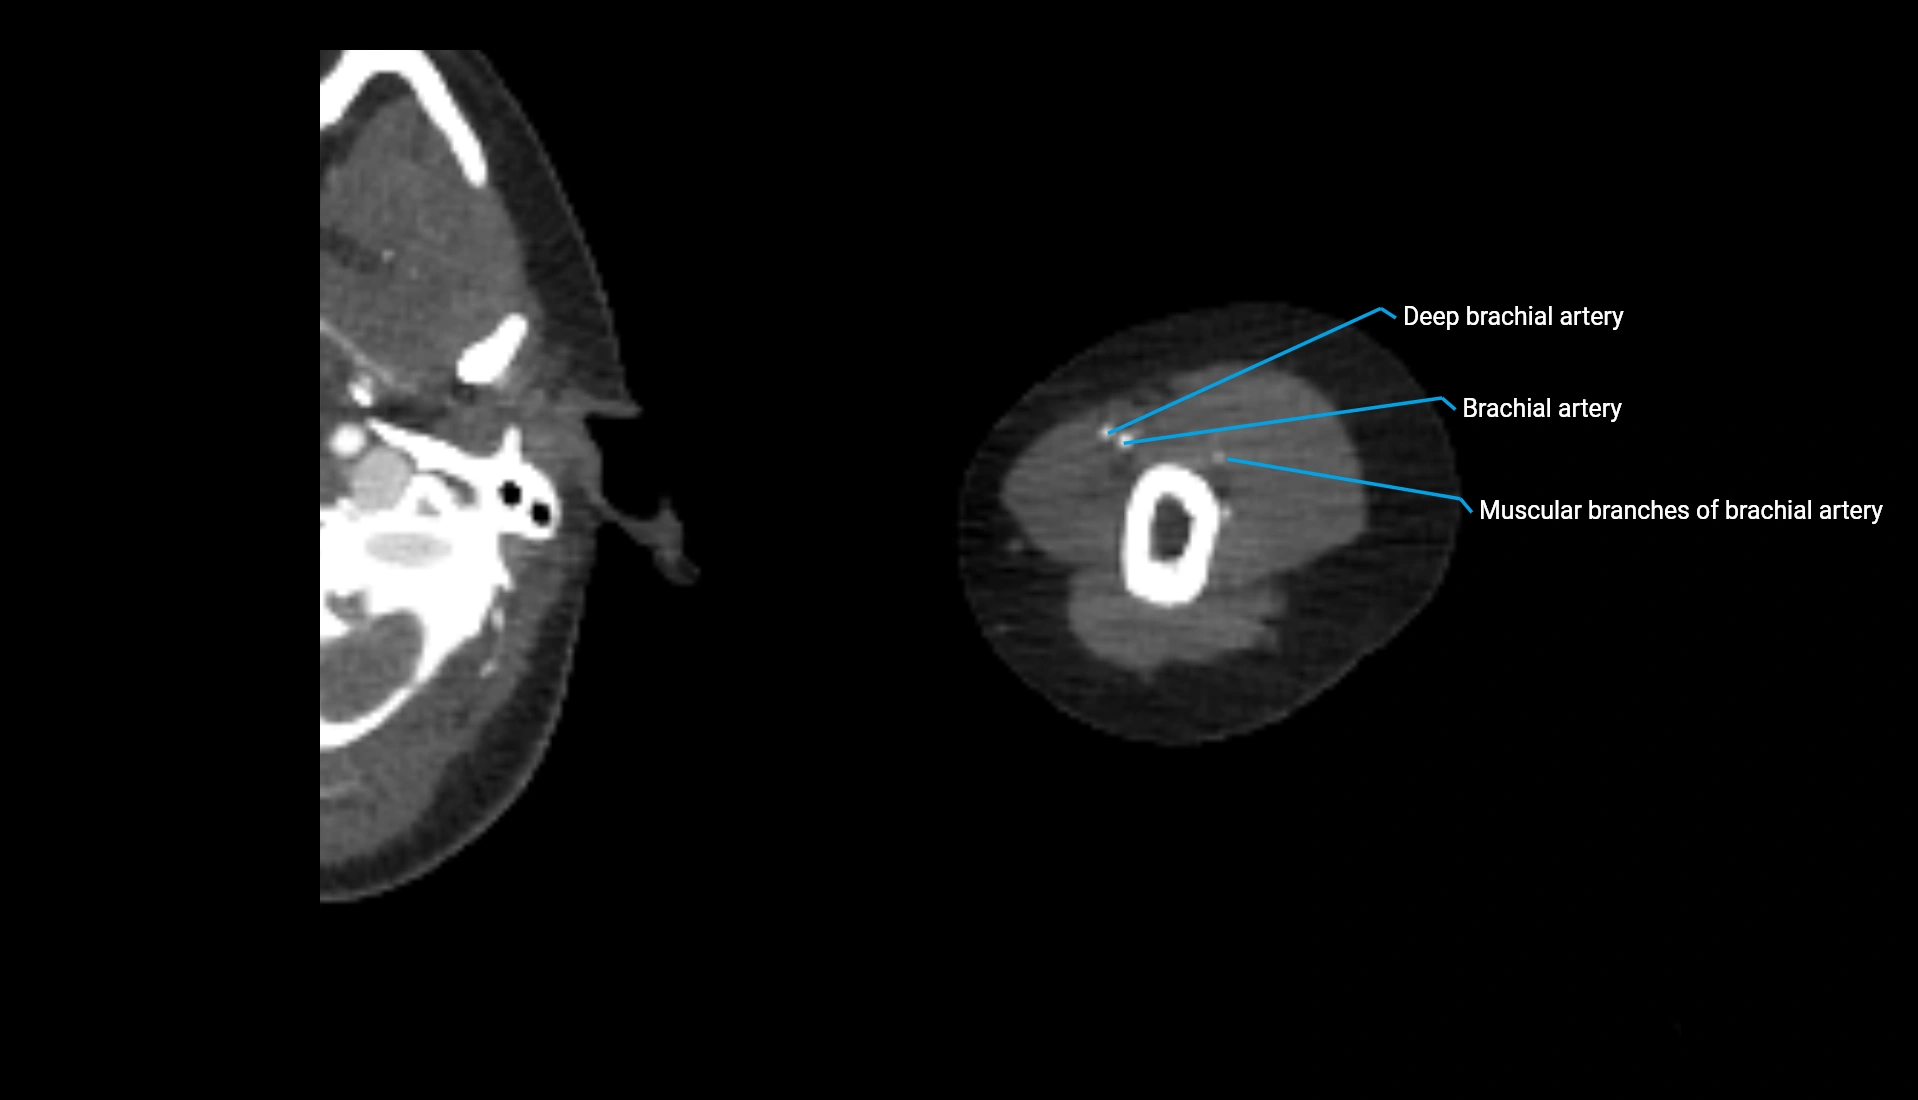

CT Appearance

Non-Contrast CT:

• Cortex: High-density, sharply defined

• Subchondral bone: Dense cancellous matrix

• Articular surface: Smooth concave contour articulating with the capitellum

• Excellent for evaluating bone integrity, alignment, and subtle fractures

Post-Contrast CT:

• Bone: No enhancement

• Joint capsule and synovium: Mild enhancement outlining the joint

• Improves contrast between soft tissues and bony margins

• Useful in detecting subtle joint abnormalities or postoperative changes